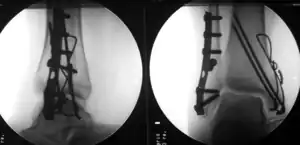

Surgically treated bimalleolar fracture

Surgical treatment will often be required, usually an Open Reduction Internal Fixation (ORIF). This involves the surgical reduction, or realignment, of the fracture followed by the implementation of surgical implants to aid in the healing of the fracture.[2]